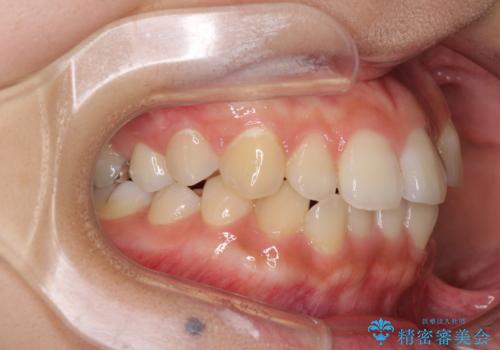

前歯の突出感とデコボコ インビザラインで改善

- 上下前歯のデコボコを気にして来院された患者様です。

インビザラインによる上下歯列の側方拡大と後方移動、IPR(歯と歯の間を削る)にるスペースの獲得により歯列を整えることとしました。

右上の小臼歯は歯根癒着をしており、様々な方法を試みるも動かすことができませんでした。

それでも奥歯のかみ合わせに不自由はなく、歯列をきれいに整えることができました。